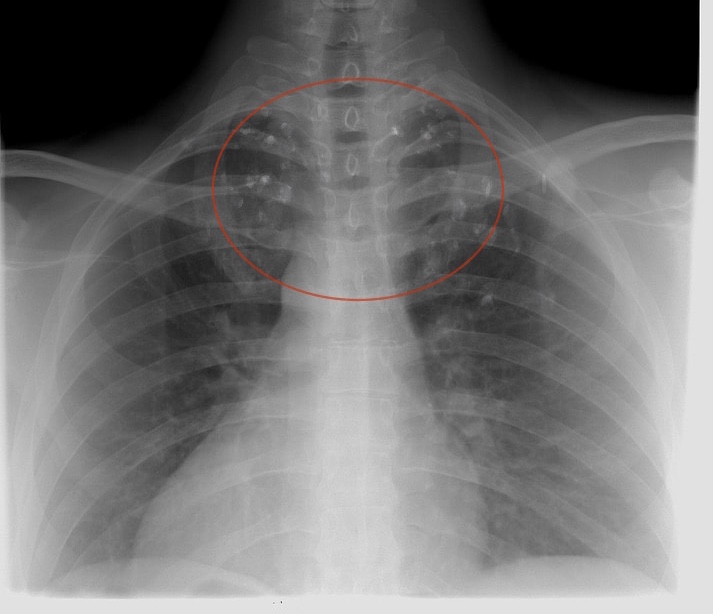

正在前往办公区的SCP-CN-2445

今天是站点的常规体检日,医务部从早上开始为设施所有人都依次做了全身检查。站点大多数人除了久坐病之外基本没什么大问题。一直持续到给素博士做检查……一开始只是因为塑料袋的原因耳鼻喉检查不太方便。可当我们做胸透的时候……打出的X光片显示他体内靠近颈部的位置有很多散射状分布的白色异物。我最开始觉得可能是没拍清造成的模糊,可是几遍下来结果是一样的。我们胸透用的X光机使用前经过多次检查,故障的可能性几乎为0。在这之后,我对着这张片子看了一下午,越看越不对劲,紧接着我找到了素博士前两年的胸透片子:两年前,素博士的胸透还是正常的。一年前的片子(素博士被困在塑料袋里那年)只是显示锁骨处有极少的白色异物,不细看根本看不见,当时我们就给忽略了。所以,我得出一个可怕的结论:它在扩散。

可随后我得出的结论更加可怕:这些白色异物其实是较大的塑料微粒,就是构成塑料袋的那种塑料微粒。